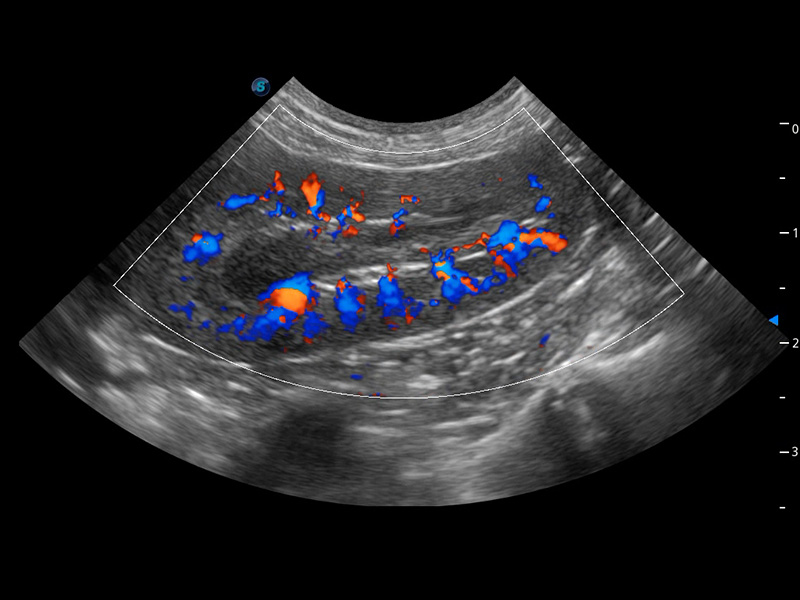

4T血流成像 微察秋毫

融合不同血流成像技术的优势,即可以提升血流成束性,同时可提高血流的视觉敏感性。

PDI 能量多普勒血流

提供高灵敏度和空间分辦率的血流图像,获得更加真实和丰富的诊断信息。

SR Flow 高分辨率血流成像

能够清晰显示细小、低速血流图像,获取传统彩色多普勒技术难以得到的细节和信息。

Micro F 显微血流成像

通过创新的Matrix E自适应滤波器和超长时间域算法,极大提升超低速微细血流的检出能力,同时更精准地滤除软组织和噪声信号,为兽用医生提供以往无法通过常规血流获得的疾病诊断信息。

Bright Flow 立体血流成像

在传统二维血流成像的基础上,呈现血流的立体感,具有动感的生命力之美。精确区分不同血管的空间关系,提高了血流的视觉敏感性。

优异的基础图像

(犬)四腔心血流

(犬)肾脏血流